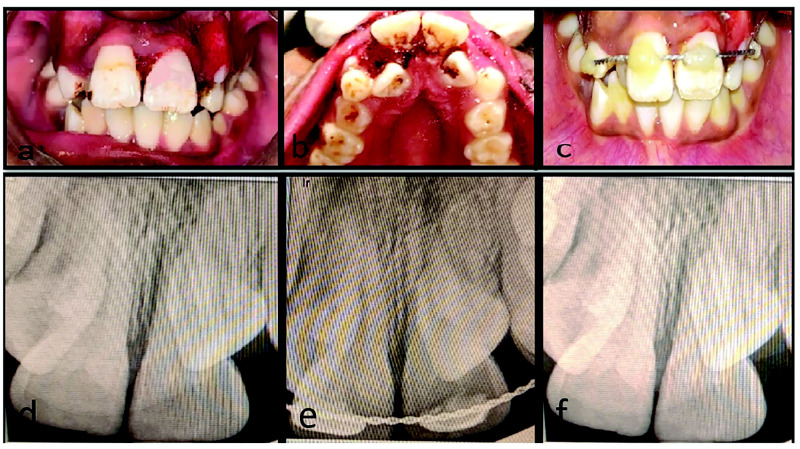

Dental injury is a common anesthesia-related adverse event, with a high incidence of damage to teeth and surrounding tissues during oro-endotracheal intubation. Poor oral hygiene, compromised periodontium, faulty or loose prosthesis, proclined maxillary incisors along with increased difficulty level of airway management, improper use of laryngoscope, and use of maxillary anterior teeth as a fulcrum for achieving accessibility to the airway are all risk factors for iatrogenic dental injury. This type of injury provides additional physical and psychological trauma to patients who have already undergone medical surgical procedures. The consequences of such mishaps might potentially result in medico-legal suits and financial claims. The present case series described three cases of managing iatrogenic dental lesions during oro-endotracheal intubation, after obtaining written informed consent, as well as methods for preventing such accidental injuries. This study emphasized the importance of collaboration between medical and dental professionals in preventing and successfully managing accidental dental injuries.